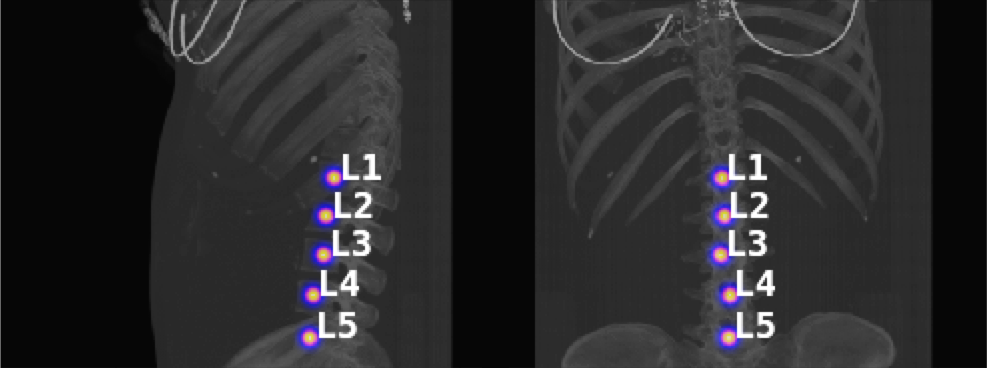

The benchmark dataset used in Section 3 of our work is mostly spine-centred, and the naive maximum intensity projections contain no occlusions. However, in certain full-body scans, the spine is obstructed by the ribcage in a MIP of the entire scan, or the spine is not spatially centred in both the views, thus not taking full advantage of Btrfly net’s view fusion (cf. Fig. 6a). Such cases can be handled by a introducing a pre-processing step before the Btrfly net in the form of an ‘object-detection’ network.

For such scenario, we construct the MIPs in two stages. The first MIP is constructed on the entire scan. On this, we use a single-shot object detection (SSD) inspired architecture [1] trained to identify occluded spines (cf. Fig. 6a). Once the spine is located, we construct the second pair of MIPs based on the spine-slices, which are then used as inputs to the Btrfly net (cf. Fig. 6b,c). The ground truth for the SSD net can be constructed from the ground truth annotation of the vertebral centroids. We use a generic 16-layer residual CNN with an SSD extension. This use-case is illustrated on a scan from the training set of the xVertSeg [2] dataset. Note that we used the xVertSeg data only for inference and not for re-training the network. The centroids of the vertebrae are obtained from the maximum point of the distance transform of the segmentation map (xVertSeg has voxel-level annotations from L1 to L5).